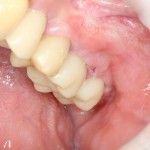

Имплантация и остеопластика: вместе или врозь? Часть II плюс Ankylos, плюс Geistlich